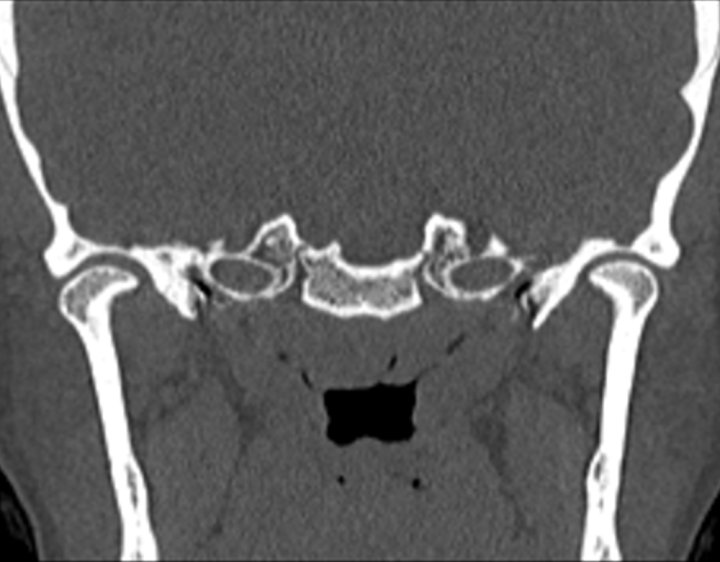

Click any image for labels.